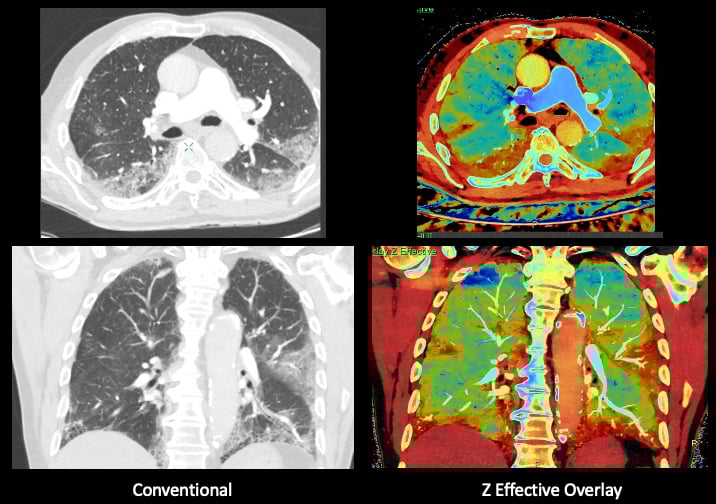

This photo gallery shows the variety of radiological presentations of COVID-19 (SARS-CoV-2) in medical imaging, including computed tomography (CT), radiograph X-rays, ultrasound, echocardiograms and magnetic resonance imaging (MRI). The radiology images show examples of typical COVID pneumonia in the lungs and the numerous complications the virus causes in the body in multiple organs, including the brain, kidneys, heart, abdomen and vascular system.

Ultrasound, especially hand-held ultrasound imaging devices, have become a primary imaging modality for novel coronavirus because of the ease to bag the device and sterilize it after use. CT and mobile X-ray systems are also used as front-line imaging systems for COVID-positive or suspected COVID patients.